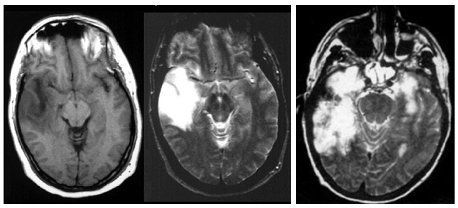

Aviles Fig4 (image/jpeg)